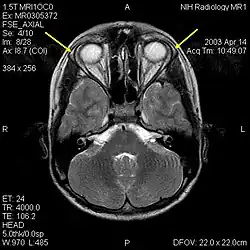

| MRI of the brain of 12-year-old boy with triple-A syndrome showing hypoplastic lacrimal glands (yellow arrows) | |